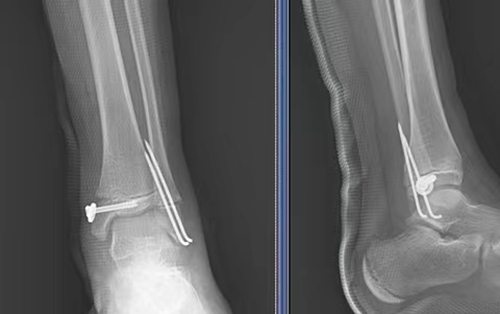

△術(shù)后X線

充分術(shù)前準(zhǔn)備后,在麻醉科的保駕護(hù)航下,骨科團(tuán)隊(duì)進(jìn)行了微創(chuàng)手術(shù),手術(shù)切口僅1CM。手術(shù)順利完成,明明被轉(zhuǎn)入兒童重癥監(jiān)護(hù)室監(jiān)護(hù)治療,在醫(yī)護(hù)團(tuán)隊(duì)的精心照顧下,病情逐漸平穩(wěn)。